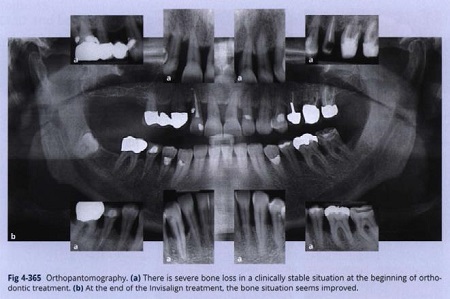

Chẩn đoán hình ảnh khi kết thúc điều trị quanh răng đã chỉ ra sự tiêu xương nghiêm trọng, nhưng là một tình trạng ổn định trên lâm sàng (hình 4-365).

Mô quanh răng được ổn định cả trước và sau điều trị với máng chỉnh nha trong suốt (Hình 4-366).